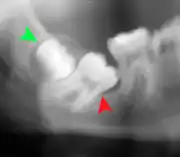

Coronectomy

Coronectomy is a procedure where the crown of the impacted wisdom tooth is removed, but the roots are intentionally left in place. It is indicated when there is no disease of the dental pulp or infection around the crown of the tooth, and there is a high risk of inferior alveolar nerve injury.[31]

Coronectomy, while lessening the immediate risk to the inferior alveolar nerve function has its own complication rates and can result in repeated surgeries. Between 2.3% and 38.3% of roots loosen during the procedure and need to be removed and up to 4.9% of cases require reoperation due to persistent pain, root exposure or persistent infection. The roots have also been reported to migrate in 13.2% to 85.9% of cases.[31]